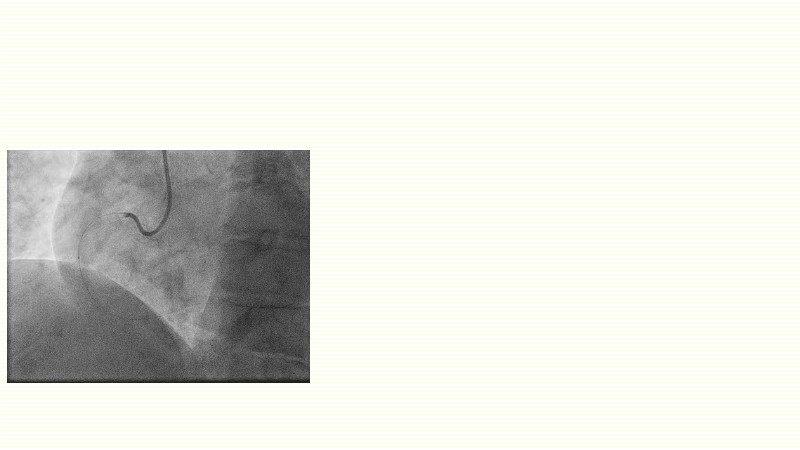

This EuroPCR 2025 session challenges the conventional approach to bifurcation PCI and dissection management. Learn why drug-coated balloons (DCB) may offer better long-term outcomes in cases where stents fall short, how DCBs can simplify bifurcation strategies, and why it’s time to rethink which dissections really need stenting. Through data, case examples, and clear decision-making insights, you'll gain the confidence to broaden your DCB practice where it truly matters.

- To reflect on when to use drug-coated balloons and stents

- To evaluate which dissection to leave and which to stent